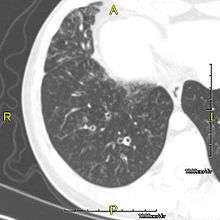

The main consequence of impaired ciliary function is reduced or absent mucus clearance from the lungs, and susceptibility to chronic recurrent respiratory infections, including sinusitis, bronchitis, pneumonia, and otitis media. Progressive damage to the respiratory system is common, including progressive bronchiectasis beginning in early childhood, and sinus disease (sometimes becoming severe in adults). However, diagnosis is often missed early in life despite the characteristic signs and symptoms.[1] In males, immotility of sperm can lead to infertility, although conception remains possible through the use of in vitro fertilization and, as well as this, there have been reported cases where sperm were able to move.[2] Trials have also shown that there is a marked reduction in fertility in female sufferers of Kartagener's Syndrome due to dysfunction of the oviductal cilia.[3]

Many affected individuals experience hearing loss and show symptoms of glue ear which demonstrate variable responsiveness to the insertion of myringotomy tubes or grommets. Some patients have a poor sense of smell, which is believed to accompany high mucus production in the sinuses (although others report normal - or even acute - sensitivity to smell and taste). Clinical progression of the disease is variable with lung transplantation required in severe cases. Susceptibility to infections can be drastically reduced by an early diagnosis. Treatment with various chest physiotherapy techniques has been observed to reduce the incidence of lung infection and to slow the progression of bronchiectasis dramatically. Aggressive treatment of sinus disease beginning at an early age is believed to slow long-term sinus damage (although this has not yet been adequately documented). Aggressive measures to enhance clearance of mucus, prevent respiratory infections, and treat bacterial superinfections have been observed to slow lung-disease progression. Although the true incidence of the disease is unknown, it is estimated to be 1 in 32,000,[4] although the actual incidence may be as high as 1 in 15,000.